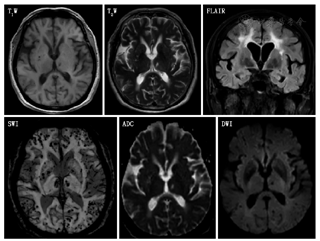

T1WI图像对不同的软组织结构有良好的对比度,适于观察软组织的解剖结构;T2WI对显示病变的信号变化比较敏感,利于观察病理变化。二者结合有助于病变的定位、定量和定性诊断。缺血性脑卒中的病灶为低信号,一般24 h后出现。脑出血病灶在急性期为高信号,恢复期和后遗期为低信号(软化灶)。

FLAIR是一种特殊序列,使脑脊液呈低信号,可避免脑脊液产生的部分容积效应及流动伪影的干扰,提高了病灶与正常组织的对比度,因此可显示脑脊液边缘易重叠的脑梗死;常规MRI不易区别SAH与脑脊液,而在FLAIR中,血性脑脊液T2值大于脑实质,信号比脑实质高,具有诊断优势,尤其对后颅凹少量出血更有诊断价值。FLAIR被广泛应用于颅脑各类疾病包括缺血性病变、外伤、出血、肿瘤、脑白质病变的诊断中[16]。急性缺血性脑卒中、外伤、脑出血、肿瘤、白质病变在FLAIR可见病灶为高信号,可以结合其他序列进行鉴别诊断。如对急性缺血性脑卒中和脑出血进行鉴别,可行T1WI检查,前者为低信号,后者为高信号;而T2WI与其相反,前者为高信号,后者是低信号;脑白质病变与急性缺血性脑卒中在T2WI和FLAIR上均为高信号,可采用DWI进行鉴别,前者在DWI为等信号或低信号,后者为高信号。

DWI是在活体上测量水分子弥散运动与成像的一种方法。DWI是从细胞水平上来观察脑组织的变化,对急性组织变化比较敏感。信号强度与组织的病理变化程度一致,是组织损伤的一种定性方法。缺血组织在发病数分钟至数小时出现表观弥散系数(apparent diffusion coefficient,ADC)下降,从而在DWI上表现出高信号[17]。急性脑出血在DWI上也为高信号,可采用T1WI和T2WI进行鉴别,CT也可以进行鉴别。

ADC也是反映体内水分子运动的一个参数,是检测水分子向各个方向弥散的平均值,水分子弥散运动越明显,ADC值增高[19]。ADC对临床早期鉴别缺血性脑卒中或炎性病变具有重要帮助(图5)。急性缺血性脑卒中ADC表现为低信号,而脑炎可为高信号。

左侧丘脑可见点状长T1、长T2信号影;两侧额顶叶及侧脑室旁白质可见多发斑片状长T1、长T2信号影,FLAIR呈高信号;SWI见两侧大脑半球弥漫性点片状低信号影部分呈融合状(图14)。

FLAIR:液体衰减反转恢复序列;SWI:磁敏感加权成像;ADC:表观弥散系数;DWI弥散加权成像

(1)腔隙性脑梗死:病灶直径3~15 mm,呈边缘清晰的圆形、裂隙状或椭圆形,MRI/T1WI呈低信号而T2WI呈高信号;急性期的DWI为高信号。陈旧性腔隙性脑梗死:在FLAIR上病灶呈低信号,周围有胶质增生的高信号。病灶主要分布于基底节、丘脑、内囊、豆状核和尾状核、脑干等脑穿支动脉供血区域。(2)多发性硬化:脑和脊髓均可有病灶,为多病灶,呈非对称性,通常有相对固定的分布模式及形态;病灶与侧脑室垂直分布;在T1WI为低信号,T2WI为高信号(煎蛋状、云雾状),FLAIR为高信号,急性期DWI呈高信号,增强后呈C形或开环状强化。